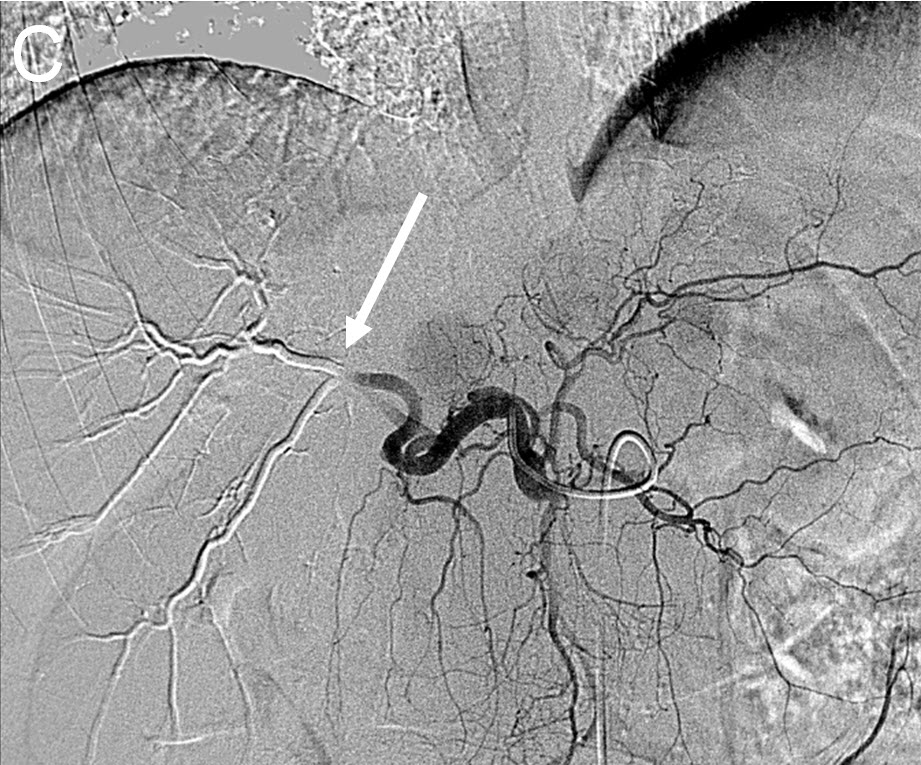

Treating Multiple Liver Tumors with Drug Eluting Beads (DEB TACE)

| (C) Angiogram after right hepatic artery(white arrow) embolization using Drug Eluting Beads (DEB TACE) |